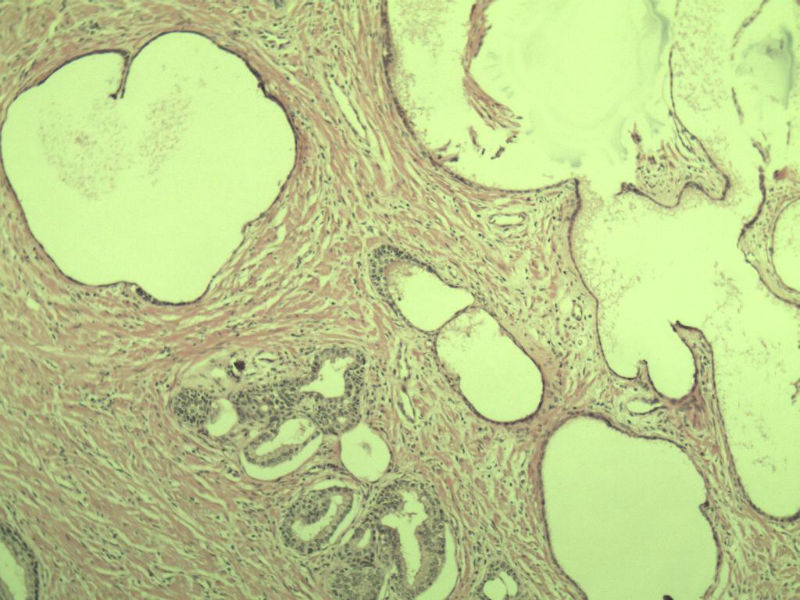

男 75岁 因排尿困难半年行前列腺切除术,体积 4 × 3 × 2.5 cm3,切面灰白,实性,质韧。请各位老师看看 有问题没? 谢谢了!

良性前列腺增生伴尿路上皮化生

前列腺增生症伴鳞化

前列腺增生伴尿路上皮鳞化及Brown巢形成,未见恶性。

前列腺增生,有腺瘤样结节形成。